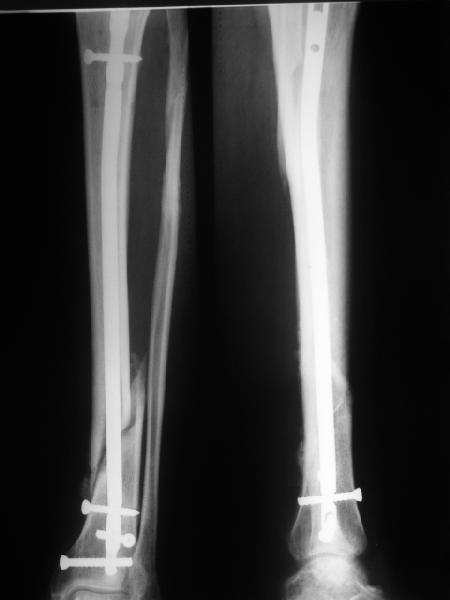

В приложении картинка пациента со сломанным внизу гвоздем. Начал лечение в другом учреждении. Еще и адвокат к тому же.

Динамизировали через 8 недель, а оно поползло больше, чем хотелось бы.

Посмотрев на клинический случай с винтообразным переломом ББ и МБ костей, возник вопрос о целесообразности динамизации фиксатора при подобном типе перлома.

Винтообразный перелом создает обширную зону межфрагментарного контакта, что является благоприятным условием для консолидации, если в ожидаемые 8-10 недель мозолеообразования не наблюдается, то динамизация приводит к *соскальзыванию* проксимального фрагмента- вторичному смещению, величина которого и определяется размером овального окна гвоздя.

Логичным, на мой взгляд, в подобной ситуации является не динамизация гвоздя, а смена гвоздя на больший размер с рассверливанием.